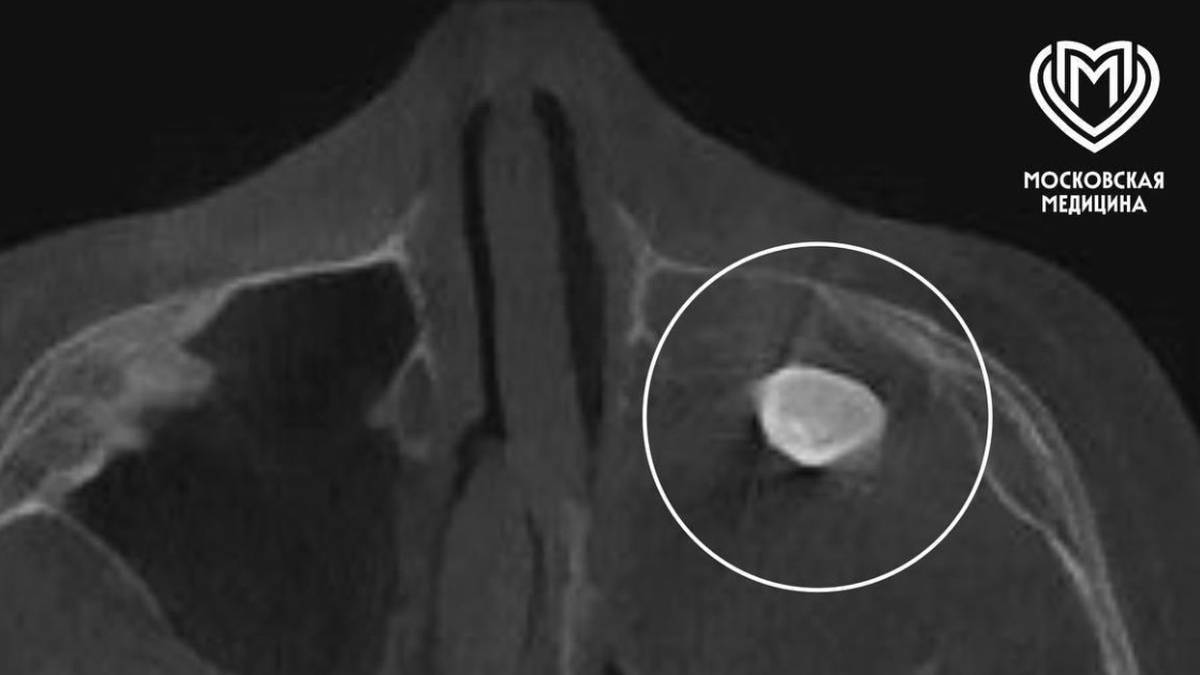

Хирурги Филатовской детской больницы Москвы удалили 15-летнему подростку зуб, который вырос в носу. Об этом во вторник, 17 марта, рассказали в столичном департаменте здравоохранения.

Мальчик обратился с жалобами на асимметрию лица и заложенность носа. Выяснилось, что в другой клинике у подростка в гайморовой пазухе нашли сформированный зуб, после чего предложили его удалить.

Несмотря на это, его родители решили обратиться за консультацией в Филатовскую детскую больницу. Там медики провели углубленное обследование и собрали консилиум.

— Мальчику нужно было провести операцию по Колдуэллу-Люку. Сделав разрез, врачи обнаружили новообразование, внутри которого и находился зуб, — добавили в Telegram-канале ведомства.